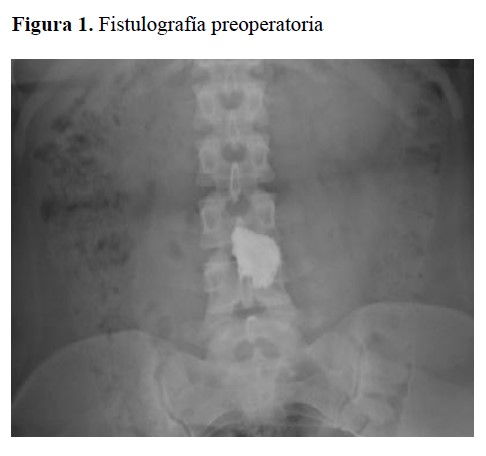

El servicio de cirugía general en el examen físico de la paciente encontró en el ombligo un orificio de 2 mm de diámetro acompañado de salida de líquido amarillo viscoso fétido que aumentaba con las maniobras de Valsalva y compresión periumbilical, asociado a eritema, rubor y calor periumbilical. Se solicitó una fistulografía al orificio encontrado en el ombligo, se canalizó para pasar el medio de contraste, en la imagen radiológica el líquido de contraste permaneció a nivel umbilical sin evidenciar alguna comunicación con vísceras huecas, por lo que la impresión diagnóstica inicial fue un COM persistente incompleto o no comunicante. (Figura 1).

Figura 1. Fistulografía preoperatoria